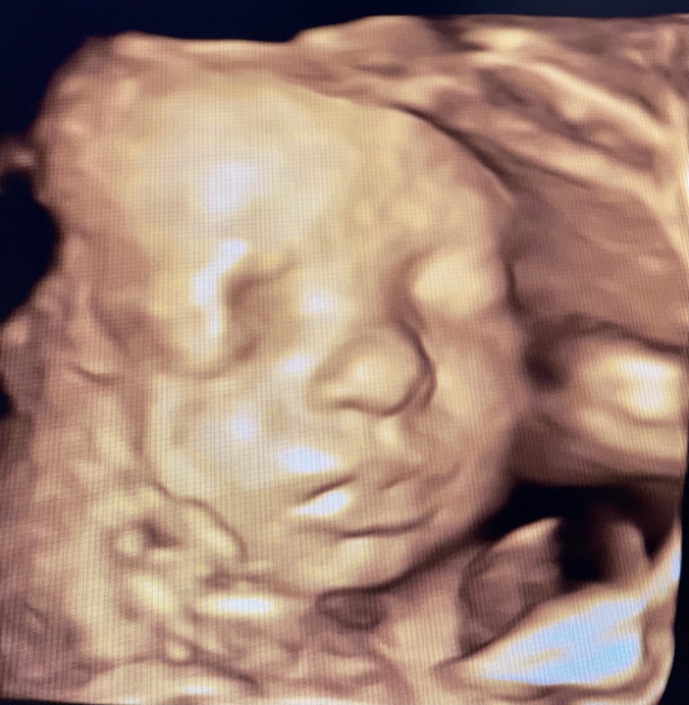

Prenatal Peek®

Prenatal Peek is the leader in 3D 4D Ultrasound. We employ only Certified / Registered Sonographers maintaining unsurpassed standards in 3D ultrasound. You deserve the best! Call us today.